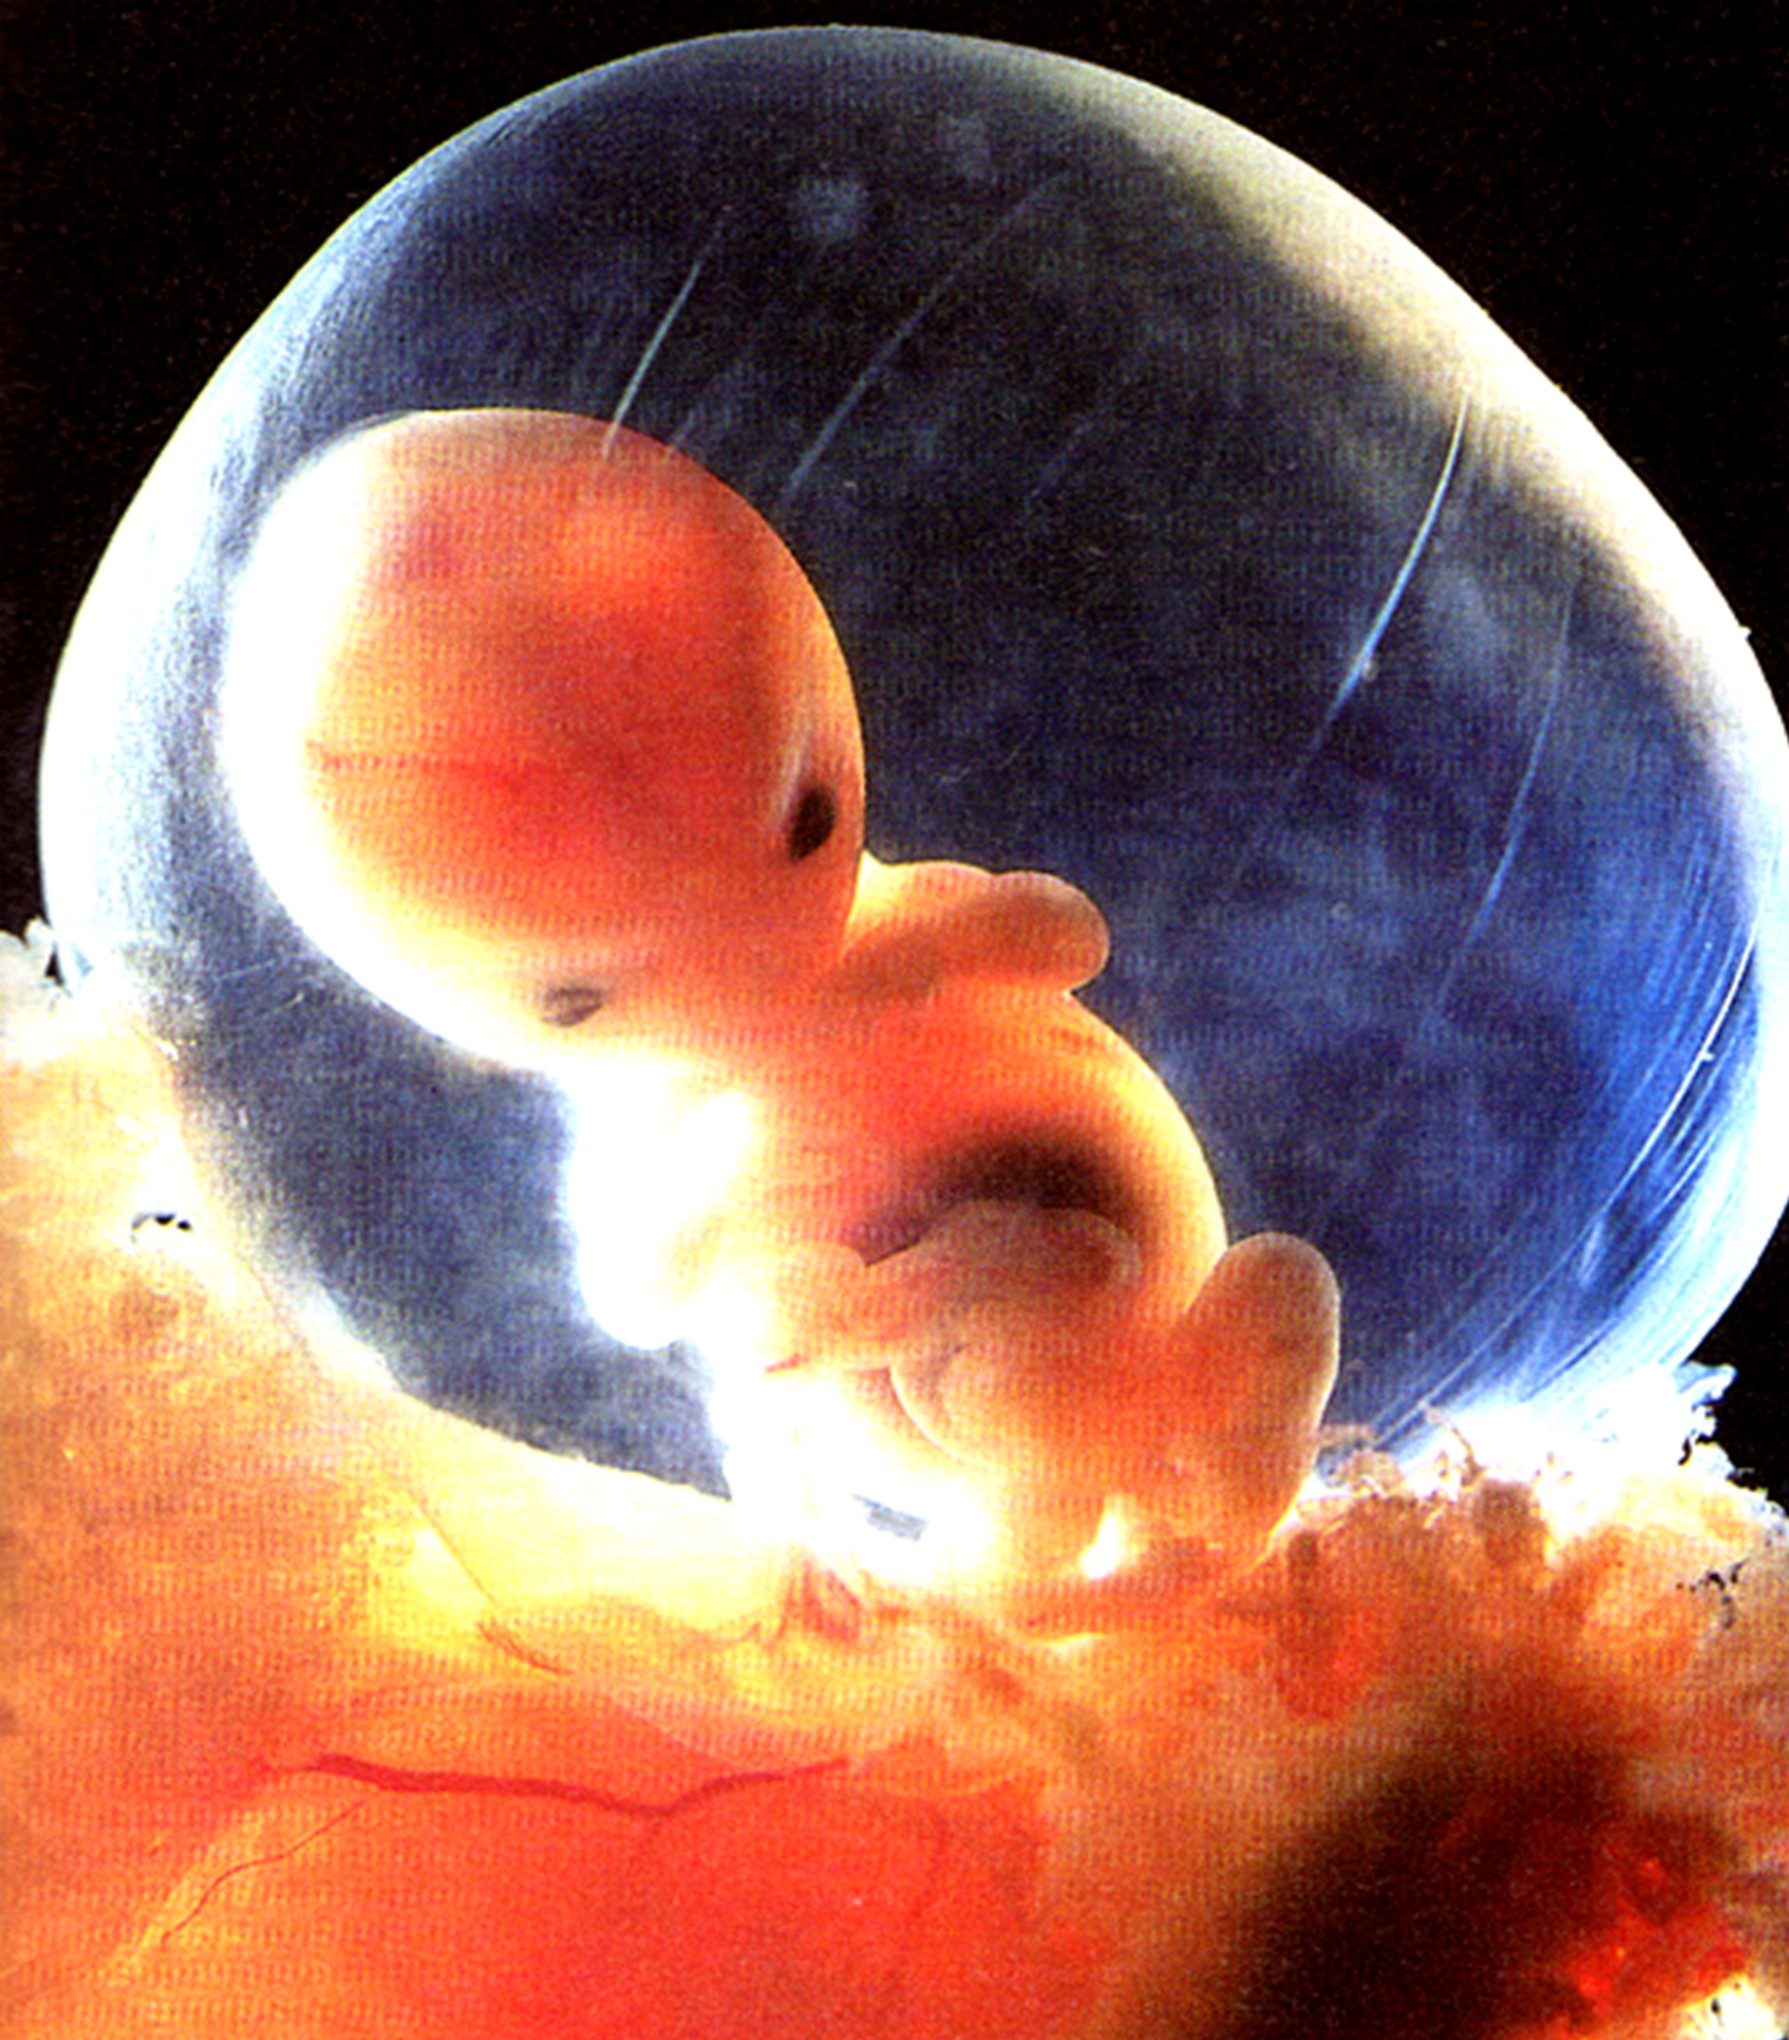

Эмбрион Леннарт Нильсон

Эмбрион Леннарт Нильсон

Эмбрион Леннарт Нильсон